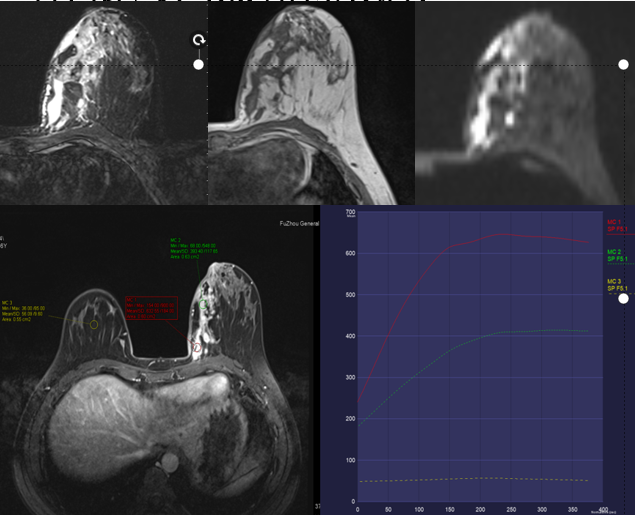

MG/CT:

乳腺炎:包括急、慢性乳腺炎和乳腺脓肿,多见于产后哺乳期妇女,急性乳腺炎常有典型的临床症状-红、肿、热、痛;若治疗不及时可形成慢性乳腺炎或乳腺脓肿。MG 表现片状致密影,边缘模糊,患处皮肤水肿增厚,皮下脂肪层模糊;MRI-T1WI 表现为片状低信号,T2WI 高信号,信号强度不均匀,边缘模糊,皮肤水肿、增厚,增强 MRI 通常表现为轻至中度强化,且以延迟强化为主。